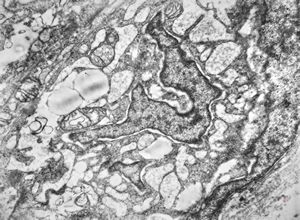

F,56y. | nemaline myopathy v.s.